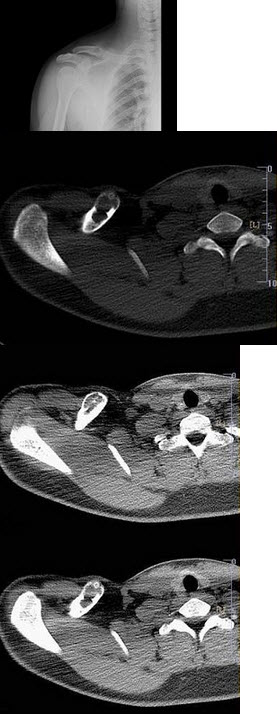

165、单项选择题

女,50岁,因右侧骶髂关节疼痛半年伴左下腹部疼痛,血尿1天,X线检查如图所示,最可能的诊断是()

A.右侧骶髂关节炎

B.右侧致密性骶髂关节炎

C.左侧输尿管下端结石

D.右侧致密性骶髂关节炎;左侧输尿管下端结石

E.以上均不正确